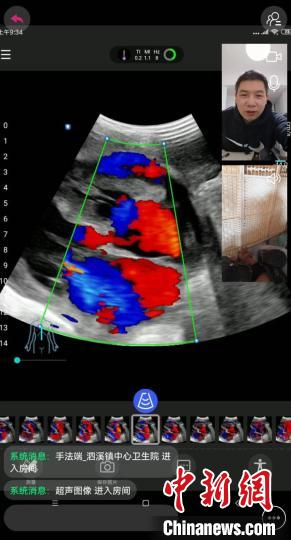

距离上海600公里外、浙江和福建交界处一个偏僻山村的患者,在家里及时得到了准确的超声检查。 上海市第十人民医院供图

上海市第十人民医院超声医学科专家彭成忠最近被封控在家。浙江省泰顺县泗溪镇卫生院全科医生王德平发来会诊请求:“一位行动不便的病人出现呼吸困难,需要到他家里做个超声检查。”彭成忠拿出手机,打开会诊软件。王德平带着掌上超声机器在患者家里,和上海专家进行了实时的连线会诊。超声机器扫描过的位置,图像直接呈现在彭成忠的手机上。疫情防控之下,距离上海600公里外、浙江和福建交界处一个偏僻山村的患者,在家里及时得到了准确的超声检查,两地医生明确了患者呼吸困难的根本原因:心功能衰竭和心包积液,为后续的治疗指明了方向。